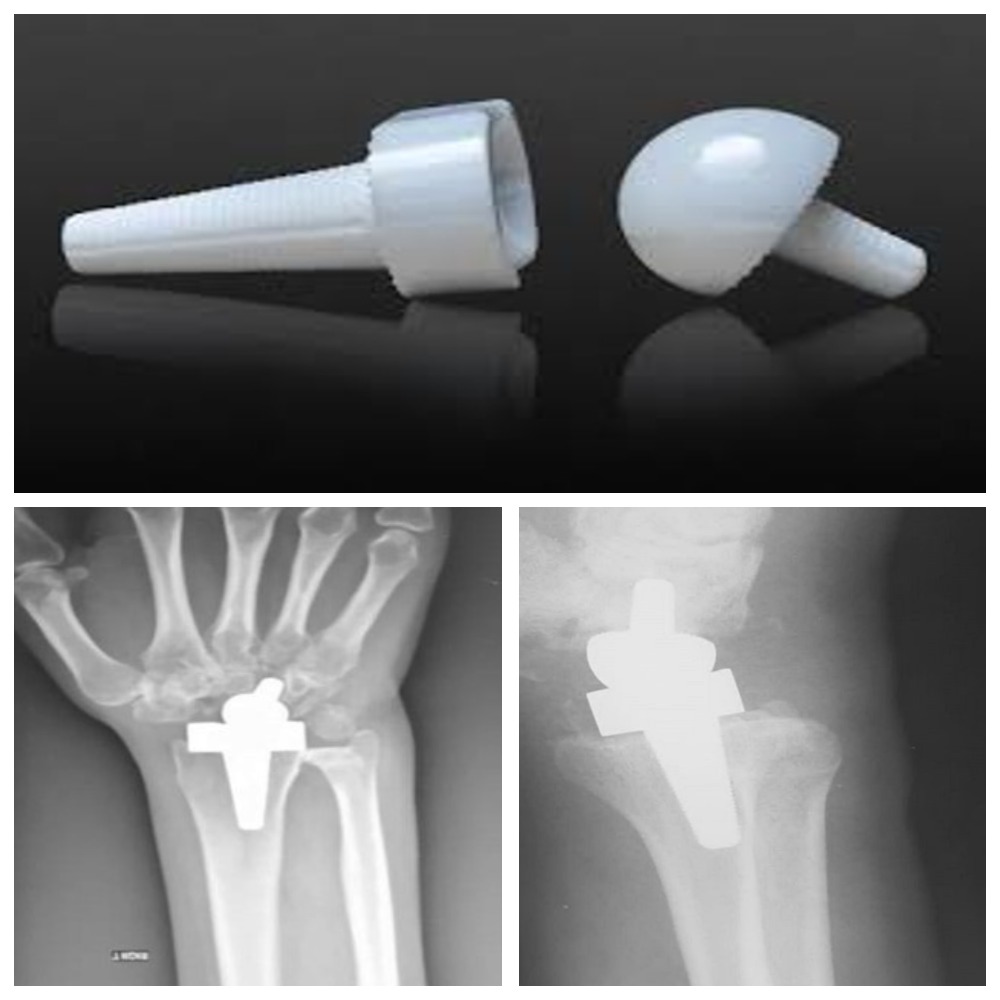

Замена же лучезапястного сустава является операцией по-своему уникальной, однако в нашем центре она проводится регулярно. Хирурги выполняют её в том случае, если человека мучают постоянный дискомфорт и изматывающие боли, руки теряют прежнюю подвижность, даже простые бытовые манипуляции даются ему с большим трудом, а все консервативные способы лечения уже исчерпаны или вовсе невозможны (к примеру, вследствие травм).

Эта методика позволяет сохранить функцию и объём движений сустава, восстановить его ось и вернуть пациента к полноценной активной жизни.

На фото вверху вы видите руки пациентки сорока пяти лет, которая жаловалась на постоянные боли в лучезапястном суставе и ограничение движения в течение последних десяти лет. Ранее она неоднократно получала травмы руки при занятиях спортивной гимнастикой. Рентгенография показала выраженный артроз, что в дальнейшем подтвердилось на исследовании КТ. Пластическими хирургами НМИЦ ВМТ им. А.А. Вишневского МО РФ был установлен эндопротез лучезапястного сустава Moje MBW. Функциональный результат уже через 6 месяцев - полное восстановление подвижности кисти. Пациентка, довольная результатом, вернулась к своей обычной жизни и любимой работе: она является преподавателем музыки.